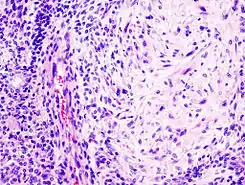

![]() Adenoma pleomórfico con epitelio mixto (izq) y componentes celulares mesenquimatosos (der). Estos últimos exhiben apariencia mixofibroso y cierta diferenciación condromatosa. | ||

Bajo el microscopio, tienen una apariencia altamente variable, incluso dentro de un mismo tumor. Clásicamente, es un tumor bifásico y se caracteriza por tener una mezcla de epitelio poligonal y elementos mioepiteliales de forma de huso en un trasfondo de estroma muy variable que puede ser mucoide, mixoide, cartilaginoso o hialino.[1] Los elementos epiteliales pueden acomodarse en forma de estructuras ductales, o bien en forma laminar, agrupados o en filamentos que se entrelazan. Las células que conforman el epitelio son de dos tipos, luminales (epiteliales) y no-luminales (mesenquimatosos) y pueden también ser poligonales, laminares o estrellados (por ello el término pleomórficos). Puede haber presentes áreas de metaplasia escamosa y perlas epiteliales.

El tumor no está envuelto, pero está por lo general rodeado de una seudo-cápsula de grosor variable. El tumor se extiende en sus dimensiones a velocidades variables, entrando en el parénquima glandular normal, formando un frente de forma de dedo, aunque ésta variación no implica una transformación maligna.